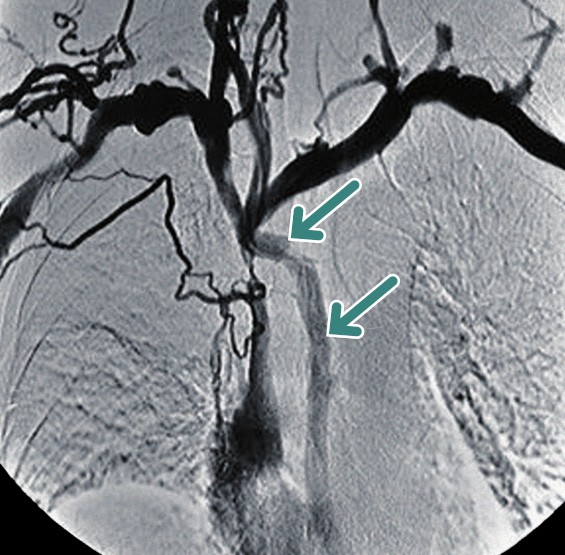

Sindrome della Vena Cava Superiore

Questa sindrome è causata dall’ostruzione del flusso sanguigno nella vena cava superiore, con conseguente aumento della pressione venosa a monte. I sintomi caratteristici sono cefalea, edema al volto e al collo (“edema a mantellina”) e turgore delle vene giugulari.

La vena azygos svolge un ruolo cruciale nello stabilire un circolo collaterale per bypassare l’ostruzione. La presentazione clinica e la gravità della sindrome dipendono dalla localizzazione dell’ostacolo rispetto al suo sbocco:

- ostruzione al di sotto dello sbocco della vena azygos: il compenso è inefficace. Il sangue deve defluire attraverso le vene lombari e la vena cava inferiore, causando la comparsa di vene dilatate a livello addominale;

- ostruzione al di sopra dello sbocco della vena azygos: il compenso è parziale. Si aprono vasi collaterali (vena succlavia, vene intercostali) che portano il sangue alla vena azygos, la quale rimane permeabile e riesce a condurre parte del flusso alla vena cava superiore a valle dell’ostruzione;

- ostruzione allo sbocco della vena azygos: è lo scenario più impegnativo. Il sangue deve raggiungere la vena cava inferiore attraverso le vene superficiali toraciche (mammaria, intercostali), in cui il flusso si inverte, per poi passare alle vene epigastriche e all’iliaca esterna.

L’eziologia è prevalentemente neoplastica (80% dei casi), con il carcinoma polmonare microcitico che rappresenta la causa più comune.